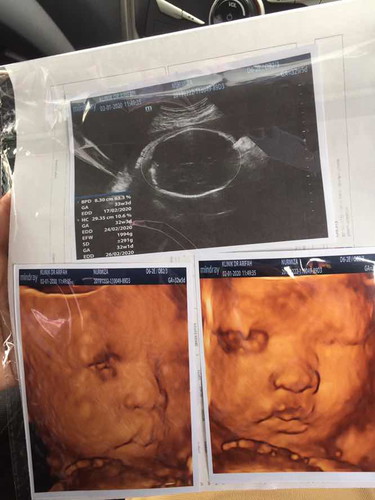

Haritu nak buat scan 4D masa kandungan 30w tapi tak lepas sebab dapat tahu baby songsang. sedih sangat tapi banyak ikut tips dari DR. Harini pi scan kandungan nak masuk 33w, Alhamdullilah baby dah pusing dan DR cakap dah duduk cantik di tempat yang sepatutnya. Syukurrrrr..... siap pakej dapat buat 4D harini. Doakan saya ya yang tak lama lagi dah. Dipermudahkan dan dilancarkan urusan saya dan baby dari A-Z. Saya single mom jadi kena kuat lebih???